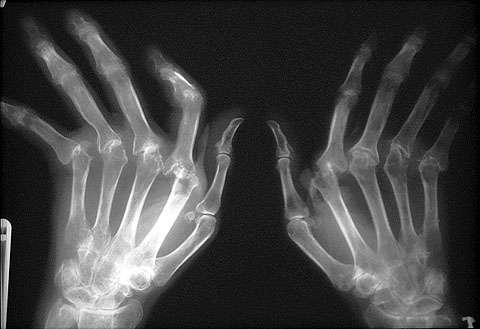

Las deformidades que tiene el señor Raúl en pies y manos son muy severas, vive con dolor constante y esto le impide realizar sus actividades diarias adecuadamente, comenta la Maestra Patricia Velázquez Tudón, Coordinadora de Rotaciones Clínicas, en el Campus Chapultepec de UVM.

Don Raúl Pérez siente consuelo cuando comenta que en la clínica de Fisioterapia le informaron que es posible detener el ciclo evolutivo que tiene su problema de artritis, “eso sería maravilloso porque hace unos meses atrás yo pensaba que ya no iba a poder moverme. Los dedos de mis manos están zafados, los tenía muy separados, pero con la rehabilitación voy sintiendo mejoría. Mi madre vive en Cancún, pensé que ya no podría volver a verla, pero con la atención que estoy recibiendo creo que sí podré visitar a mi mamá”, señala el señor Raúl.

La Artritis Reumatoide es una enfermedad autoinmune, no se sabe qué la causa; la sintomatología que presenta el paciente, comenta la Maestra Velázquez Tudón, son tres o más articulaciones que se inflaman (sobre todo en dedos y manos), rigidez matutina de las articulaciones (es decir que cuando se levantan se sienten “tiesos”) de 30 minutos de duración y, dolor a la compresión de las articulaciones.

La Artritis Reumatoide no tiene cura, ya que es una enfermedad degenerativa, “se puede hacer más lento el proceso y prevenir en lo posible las deformidades. El tratamiento farmacológico es decisión del médico pero hay varios medicamentos como anti-inflamatorios no esteroideos, los esteroides, los fármacos modificadores de la enfermedad, diversos medicamentos específicos, la terapia biológica, el tratamiento combinado y el tratamiento quirúrgico”, señaló la docente de UVM.